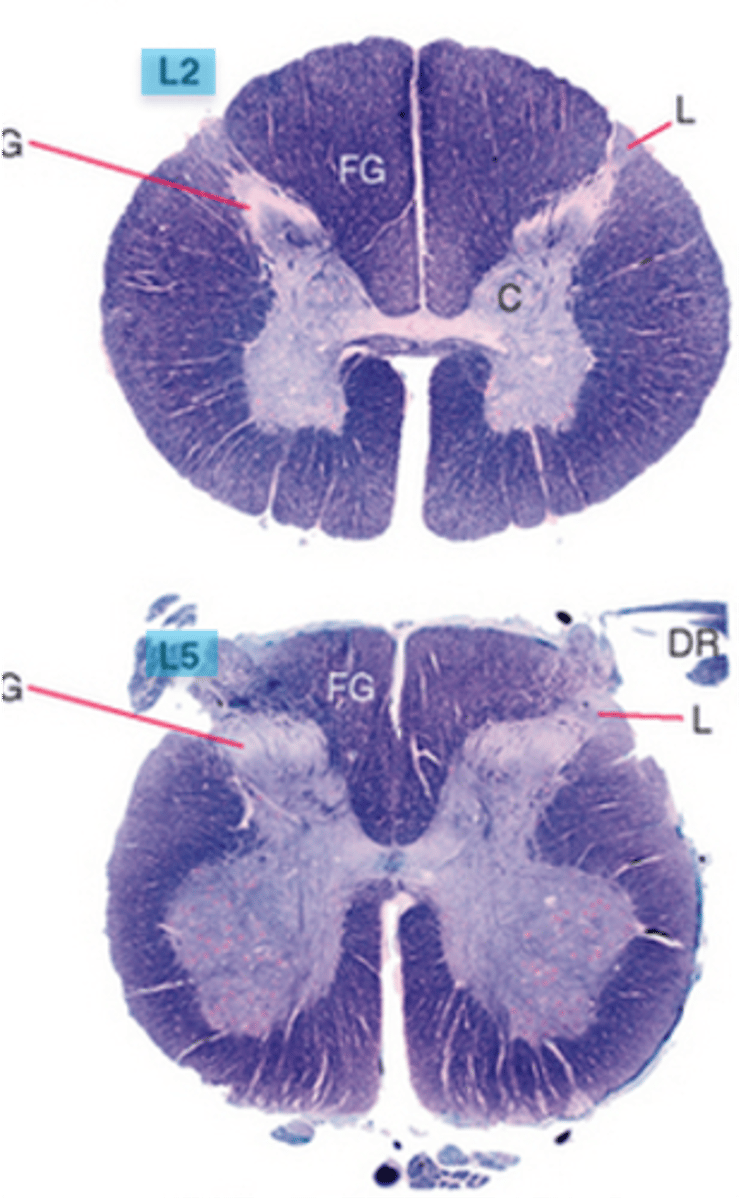

which division of the spinal cord is round, has less white matter than any other levels, has large anterior and posterior horns forming an enlargement throughout the entire division?

lumbar; lumbosacral enlargement from T11-S1

which division of the spinal cord is the most round and smaller than the lumbar division, mainly containing gray matter, but also a thin shell of white matter?

sacral